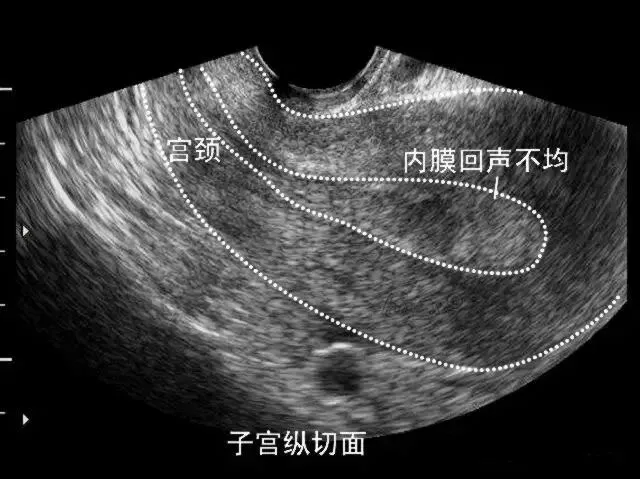

子宫内膜癌

●是指发生于子宫内膜的癌,又称宫体癌。

●二维超声表现:子宫内膜增厚、当病变累及肌层时局部内膜与肌层界限不清、早期子宫外形轮廓多无明显改变。

弥漫性子宫内膜癌声像

子宫内膜癌侵犯浅肌层声像